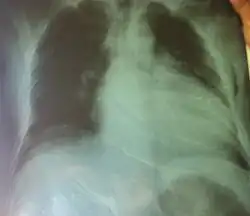

Im Röntgen-Thorax ist der Herzschatten verbreitert. In der Echokardiographie und in der Kernspintomographie sieht man eine Erweiterung der Ventrikel und der Vorhöfe. Die Wand des linken Ventrikels ist meist verdünnt, der linke Ventrikel kugelig umgeformt und allseits vermindert beweglich (kontraktil).

Die Auswurffraktion ist reduziert. Der Abstand zwischen vorderem Mitralsegel und Septum ist vergrößert. Oft liegen eine Mitralklappeninsuffizienz und eine Trikuspidalklappeninsuffizienz vor.